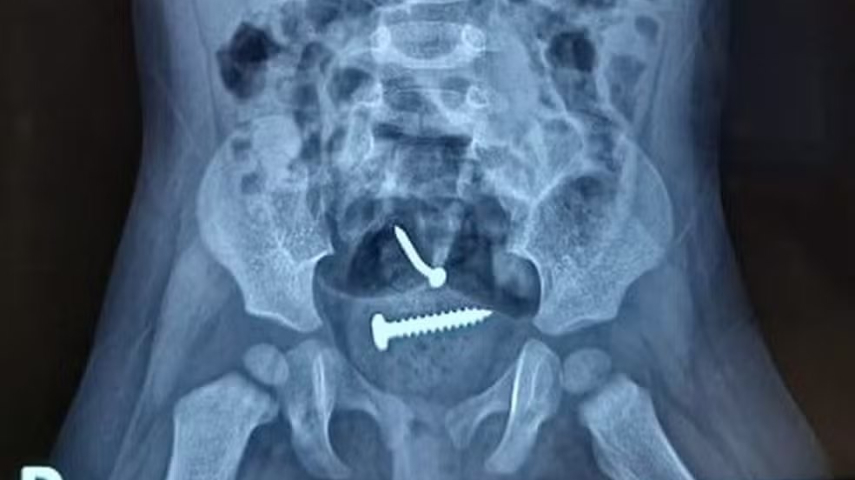

Laudo médico diz que bebê que engoliu parafuso não foi violentada; pai foi solto | Foto: Reprodução

O laudo médico da bebê de 1 ano, que estava com um prego e parafuso dentro do corpo, revela que não houve violência sexual. O suspeito de ter agredido mãe e filha prestou depoimento na delegacia da cidade de Pedro II e negou ter abusado da bebê.

A sua companheira também negou, que o pai tenha cometido algo contra a criança. O laudo também mostrou que a criança engoliu os objetos e que os mesmos foram expelidos de forma natural, não precisando de intervenção cirúrgica.